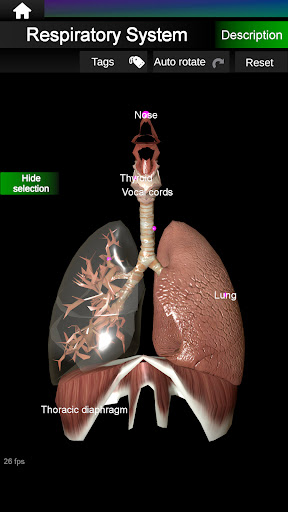

* Respiratory system, which includes the trachea, bronchi, lungs and an animation of this system.

* Easy to access and navigate (zoom, 3D rotation).

* Hide or show information.

* Descriptions of each organ.